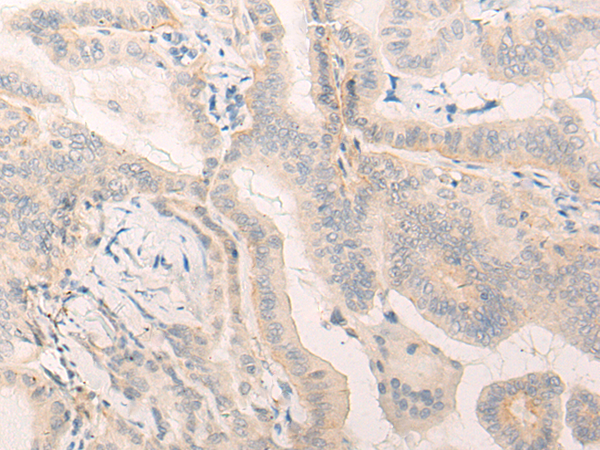

The image is immunohistochemistry of paraffin-embedded Human prostate cancer tissue using 47101(ELANE Antibody) at dilution 1/25. (Original magnification: ?00)